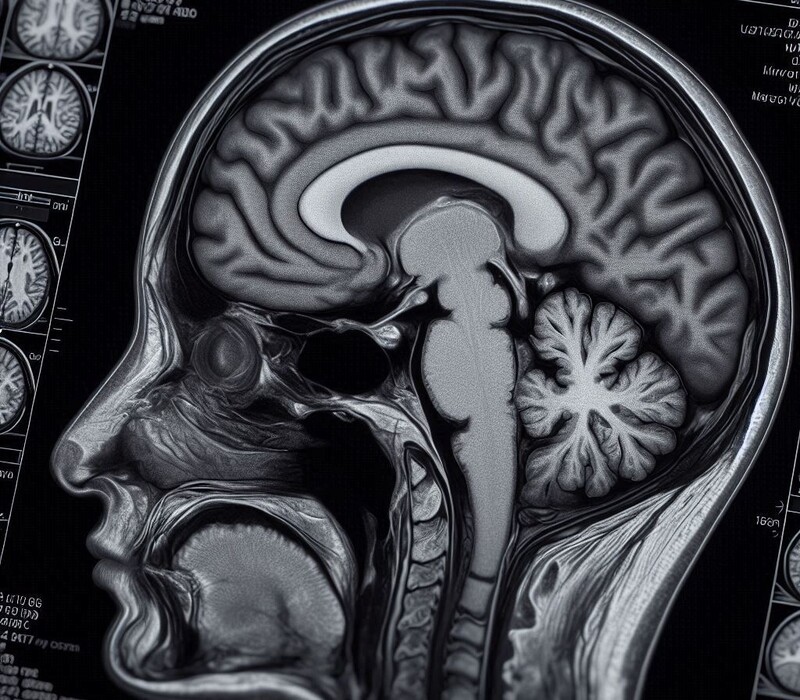

Deux révolutions qui fusionnent. L’imagerie par résonance magnétique (IRM) a été une avancée gigantesque pour la santé, permettant, à la fin du siècle dernier, de voir pour la première fois le cerveau en fonctionnement. Cette technique, qui a valu le prix Nobel de médecine à Peter Mansfield et Paul Lauterbur en 2003, a ouvert une fenêtre vers les secrets de notre organe le plus mystérieux, propulsant les neurosciences dans une nouvelle ère.

Or, une vingtaine d’années après, une nouvelle révolution bouleverse la santé : l’intelligence artificielle. Ce n'était qu'une question de temps pour que ces deux percées technologiques se rejoignent. C’est désormais le cas, grâce à une IA spécialisée conçue par des chercheurs de l’Université du Michigan aux États-Unis. Leur approche, qui automatise la détection de problèmes neurologiques lors des IRM, a été présentée le 6 février 2026 dans la revue Nature Biomedical Engineering.

L’IA en question s’appelle Prima. Il ne s’agit pas vraiment de la première intelligence artificielle pour des IRM, mais c’est la première entièrement autonome. Auparavant, d’autres IA devaient être entraînées avec des images annotées par un expert pour apprendre au modèle à reconnaître les anomalies. Contrairement à Prima, qui fonctionne davantage comme les modèles de langage (LLM) tels que ChatGPT, qui nécessitent d’être alimentés par un grand nombre de données mais qui font elles-mêmes le travail de "comprendre" ces données.

Et en plus d’analyser des images issues des IRM, Prima peut aussi analyser du texte, afin de faire le lien entre les clichés du cerveau d’un patient et son histoire médicale pour affiner le diagnostic. "Prima fonctionne comme un radiologiste, dans le sens qu’elle intègre l’information médicale du patient et les données issues des images pour avoir une meilleure compréhension de sa santé, explique dans un communiqué l’auteur de l’étude, Samir Harake. Cela lui permet d'obtenir une meilleure performance à travers un large éventail de tâches prédictives."

Les chercheurs ont entraîné Prima avec des données issues de plus de 170.000 patients ayant fait une IRM de la tête dans l’hôpital de leur université avant 2023 (pour un total de 5,6 millions de séquences d’IRM). Chaque IRM était liée à une synthèse du rapport radiologique correspondant, permettant à l’IA d’apprendre à interpréter les images toute seule. Grâce à cet entraînement, Prima est parvenue à décrire correctement les images avec un taux de succès de 94 %, étant capable ainsi de diagnostiquer 52 anomalies neurologiques, tels que les troubles vasculaires, des inflammations ou encore des infections au niveau du cerveau.

Puis, les scientifiques ont testé Prima avec tous les nouveaux patients admis à l'hôpital entre juin 2023 et juin 2024 (pour un total de 29.435 patients). L’IA est parvenue à diagnostiquer correctement chaque cas médical avec un taux de succès de 90 % en ayant accès uniquement aux images cérébrales, et à 92 % avec les images et l’histoire médicale du patient. Pour certains cas, ce taux de diagnostic était particulièrement élevé : par exemple pour les tumeurs gliales (qui concernent les cellules gliales, situées comme les neurones dans le cerveau), le taux de réussite a atteint 99,7 % !